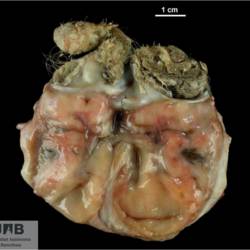

Pàgina anterior de 637 Pàgina següent 3181 total Ovine Specie: Ovine Organ: Lung Lesion: Bronchitis Lesion modifier: Bronchitis - Catarrhal Disease: Oestrosis Position: 253 (1 views) Equine Specie: Equine Organ: Ovary Lesion: Teratoma Lesion modifier: - Disease: - Not viewed Feline Specie: Feline Organ: Brain Lesion: Meningoencephalitis Lesion modifier: Meningoencephalitis - Necrotizing Disease: Toxoplasmosis Files/Expedient: N-297/07 Position: 253 (1 views) Feline Specie: Feline Organ: Brain Lesion: Encephalitis Lesion modifier: Encephalitis - Granulomatous Disease: Toxoplasmosis Files/Expedient: N-297/07 Not viewed Feline Specie: Feline Organ: Lung Lesion: Pneumonia Lesion modifier: Pneumonia - Interstitial Disease: Toxoplasmosis Files/Expedient: N-31/16 Position: 253 (1 views) Pàgina anterior de 637 Pàgina següent Títol Select...Avian (Exotic) (110)Avian (Poultry) (76)Bovine (317)Canine (935)Caprine (47)Equine (257)Feline (326)Ferret (19)General (127)Marine mammal (22)Non-human primate (20)Ovine (328)Porcine (379)Rabbit (61)Reptile (38)Rodent (28)Wildlife (91) Format Select...- (60)Abomasum (37)Adrenal gland (10)Blood (7)Blood vessel (50)Body as a whole (19)Bone (57)Bone marrow (21)Brain (93)Cloaca (1)Diaphragm (2)Ear (5)Esophagus (39)Eye (16)Fetus (12)Gallbladder (23)Gizzard (2)Heart (265)Intestine (356)Joint (32)Kidney (443)Larynx (5)Liver (326)Lung (264)Lymph node (91)Mammary gland (10)Mediastinum (1)Muscle (22)Nasal cavity (22)Nerve (7)Omasum (5)Oral cavity (63)Ovary (14)Oviduct (8)Pancreas (7)Parathyroid (5)Penis (10)Peritoneum (65)Pharynx (9)Pituitary gland (6)Placenta (7)Prostate (8)Proventriculus (3)Reticulum (1)Rumen (28)Sinus (7)Skin (181)Spinal cord (15)Spleen (105)Stomach (125)Teeth (1)Testicle (11)Thoracic cavity (31)Thymus (13)Thyroid gland (5)Tongue (32)Tonsils (11)Trachea (11)Urethra (5)Urinay bladder (61)Uterus (27)Vagina (1)Vulva (1)Yolk sac (1) Cobertura Select...- (152)Abomasitis (26)Abscess (27)Acidosis (1)Adenocarcinoma (20)Adenoma (9)Aerosacculitis (6)Agenesis (1)Agnathia (1)Alopecia (7)Amyloidosis (12)Aneurysm (6)Angiectasis (1)Anthracosis (1)Arteritis (11)Arthritis (15)Arthrogryposis (6)Artifact (4)Ascites (13)Atelectasis (8)Atherosclerosis (5)Atresia (1)Atrial septal defect (2)Atrophy (10)Autolysis (7)Bronchitis (6)Bronchopneumonia (26)Cachexia (2)Carcinoma (103)Cardiomyopathy (19)Cellulitis (2)Chemodectoma (4)Cholangiohepatitis (4)Cholangitis (19)Cholecystitis (4)Cholestasis (5)Chondrodysplasia (2)Chondrosarcoma (2)Chronic passive congestion (13)Chylothorax (2)Cirrhosis (6)Coelomitis (3)Coenurus cerebralis (4)Colitis (40)Congestion (17)Conjunctivitis (5)Coronitis (3)Cryptorchidism (3)Cyst (25)Cystitis (24)Dermatitis (69)Diaphragmatic hernia (4)Dilation (28)Discospondylitis (1)Disseminated intravascular coagulation (7)Dyschondroplasia (1)Dysplasia (29)Ectopia cordis (1)Ectopic ureter (1)Edema (55)Emphysema (5)Encephalitis (5)Endocardiosis (14)Endocarditis (26)Endometritis (5)Enteritis (118)Enterolith (6)Epulis (3)Esophagitis (14)Fasciitis (1)Fibrosis (7)Fibrous osteodystrophy (8)Fistula (1)Folliculitis (3)Fracture (2)Gastritis (34)Gingivitis (5)Glioma (8)Glomerulonephritis (21)Glossitis (25)Glycogenosis (1)Gout (8)Granuloma (2)Granulosa cell tumor (4)Hemangioma (9)Hemangiosarcoma (46)Hematoma (8)Hemoglobinuria (2)Hemopericardium (12)Hemoperitoneum (2)Hemorrhage (100)Hemosiderosis (7)Hemothorax (2)Hepatitis (78)Hernia (11)Histiocytosis (3)Hydatid cyst (11)Hydrocephalus (9)Hydrometra (1)Hydronephrosis (22)Hydropericardium (6)Hydrothorax (3)Hydroureter (5)Hyperkeratosis (8)Hyperostosis (4)Hyperplasia (37)Hypertrophy (9)Hypopigmentation (1)Hypoplasia (7)Hypopyon (1)Impaction (6)Infarction (63)Insulinoma (6)Intussusception (5)Jaundice (17)Laminitis (2)Laryngitis (2)Leiomyoma (5)Leukemia (13)Lipidosis (36)Lipoma (7)Lymphadenitis (45)Lymphadenopathy (7)Lymphangiectasia (6)Lymphangitis (5)Lymphoma (221)Malacia (11)Malignant melanoma (15)Mast cell tumor (11)Mastitis (8)Megaesophagus (2)Melanosis (3)Melena (4)Meningioma (6)Meningitis (6)Meningocele (2)Meningoencephalitis (5)Mesothelioma (5)Methemoglobinemia (2)Mineralization (10)Mucocele (5)Mucometra (1)Multilobular bone tumor (1)Mummification (3)Myelofibrosis (1)Myocarditis (4)Myositis (5)Necrosis (81)Nephritis (113)Nephroblastoma (6)Nephrosclerosis (1)Nephrosis (14)Neuritis (1)Obstruction (13)Omasitis (4)Omphalitis (1)Omphalophlebitis (7)Orchitis (4)Osteoarthrosis (5)Osteomyelitis (9)Otitis (2)Palatoschisis (3)Pancreatitis (3)Panniculitis (3)Papilloma (7)Parakeratosis (14)Patent ductus arteriosus (6)Peliosis hepatis (1)Perforation (17)Pericarditis (35)Peritonitis (39)Persistent right aortic arch (1)Pharyngitis (2)Pheochromocytoma (2)Phlebitis (2)Placentitis (6)Pleuritis (21)Pleuropneumonia (24)Pneumonia (109)Pneumothorax (3)Polycystosis (14)Polyp (5)Polyserositis (6)Posthitis (1)Proctitis (4)Prolapse (3)Prostatitis (3)Proventriculitis (1)Pyelonephritis (24)Pyometra (6)Pyothorax (4)Rhinitis (11)Rumenitis (6)Rupture (24)Salpingitis (3)Sarcoma (57)Sclerosis (1)Scoliosis (2)Seminoma (2)Sequestrum (2)Serous atrophy (14)Sinusitis (7)Splenitis (14)Splenomegaly (9)Spondylitis (6)Spondylosis (1)Stenosis (9)Stomatitis (32)Tenosynovitis (2)Teratoma (3)Thricobezoar (2)Thrombosis (16)Tonsilitis (4)Torsion (13)Tracheitis (4)Tympany (7)Typhlitis (8)Typhlocolitis (4)Ulcer (43)Urethritis (1)Urolithiasis (36)Uroperitoneum (1)Uveitis (1)Vasculitis (15)Ventricular septal defect (3)Volvulus (11) Matèria Select... - (14)- (1653)- (152)Abomasitis - Catarrhal (2)Abomasitis - Catarrhal-hemorrhagic (1)Abomasitis - Chronic (1)Abomasitis - Fibrinous-necrotizing (2)Abomasitis - Hyperplasic (5)Abomasitis - Hyperplasic - Chronic (1)Abomasitis - Necrotic (1)Abomasitis - Necrotizing (2)Abomasitis - Ulcerative (5)Adenocarcinoma (9)Aerosacculitis - Granulomatous (1)Amyloidosis - Chronic (1)Arteritis - Necrotic (2)Arteritis - Necrotizing (1)Arthritis - Chronic (4)Arthritis - Fibrinous-purulent (3)Arthritis - Serous (4)Arthritis - Subacute (1)Ascites - Serous (1)Atrophy - Serous (1)Bronchitis - Catarrhal (3)Bronchitis - Suppurative (1)Bronchopneumonia - Catarrhal-purulent (17)Bronchopneumonia - Fibrinous (1)Bronchopneumonia - Granulomatous (1)Bronchopneumonia - Purulent (1)Bronchopneumonia - Suppurative (5)Carcinoma - Adenocarcinoma (33)Carcinoma - Adenocarcinoma - Hepatocellular (2)Carcinoma - Adenocarcinoma - Mucinous (1)Carcinoma - Basosquamous (1)Carcinoma - Cholangiocellular (3)Carcinoma - Hepatocellular (4)Carcinoma - Metastatic (3)Carcinoma - Squamous cell carcinoma (13)Carcinoma - Transitional cell (2)Cardiomyopathy - Dilated (13)Cardiomyopathy - Hypertrophic (6)Cellulitis - Necrotizing (1)Cholangitis - Chronic (8)Cholangitis - Hyperplasic (3)Cholecystitis - Fibrinous-necrotizing (1)Coelomitis - Fibrinous (1)Coelomitis - Granulomatous (1)Colitis - Catarrhal (3)Colitis - Catarrhal-hemorrhagic (1)Colitis - Fibrinous (1)Colitis - Fibrinous-necrotizing (1)Colitis - Fibrinous-necrotizing (Diphtheritic) (6)Colitis - Granulomatous (2)Colitis - Hemorrhagic (4)Colitis - Hemorrhagic-necrotizing (3)Colitis - Necrotizing (2)Colitis - Ulcerative (6)Congestion - Chronic (2)Conjunctivitis - Hyperplasic (1)Conjunctivitis - Purulent (3)Coronitis - Ulcerative (1)Cystitis - Chronic (3)Cystitis - Fibrinous (1)Cystitis - Fibrinous-necrotizing (1)Cystitis - Follicular (1)Cystitis - Hemorrhagic (6)Cystitis - Hemorrhagic-ulcerative (1)Cystitis - Necrotizing (9)Cystitis - Perforated (1)Dermatitis - Granulomatous (14)Dermatitis - Hyperkeratotic (10)Dermatitis - Hyperplasic (proliferative) (1)Dermatitis - Hyperplastic (10)Dermatitis - Necrotizing (4)Dermatitis - Pustular (4)Dermatitis - Ulcerative (2)Dilation - Chronic (1)Discospondylitis - Necrotizing (1)Dysplasia - Follicular (5)Edema - Interstitial (6)Emphysema - Interstitial (1)Encephalitis - Granulomatous (1)Encephalitis - Nonsuppurative (1)Endocardiosis - Mitral (7)Endocardiosis - Mitral - Chronic (5)Endocarditis - Valvular (6)Endocarditis - Valvular - Mitral (7)Endocarditis - Valvular - Pulmonic (1)Endocarditis - Valvular - Subacute (1)Endocarditis - Valvular - Subaortic (5)Endocarditis - Valvular - Tricuspid (4)Endometritis - Purulent (3)Endometritis - Purulent-hemorrhagic (2)Enteritis - Catarrhal (23)Enteritis - Catarrhal - Acute (1)Enteritis - Catarrhal-hemorrhagic (5)Enteritis - Catarrhal-hemorrhagic - Acute (2)Enteritis - Fibrinous (16)Enteritis - Fibrinous - Acute (3)Enteritis - Fibrinous-necrotizing (7)Enteritis - Granulomatous (14)Enteritis - Granulomatous - Chronic (1)Enteritis - Granulomatous - Multifocal (1)Enteritis - Hemorrhagic (17)Enteritis - Hemorrhagic - Acute (1)Enteritis - Hemorrhagic-necrotizing (1)Enteritis - Hyperplasic (proliferative) (4)Enteritis - Necrotizing (4)Enteritis - Necrotizing - Acute (1)Enteritis - Necrotizing - Hemorrhagic (1)Enteritis - Necrotizing-ulcerative (2)Enteritis - Ulcerative (1)Enteritis - Ulcerative-hemorrhagic (1)Esophagitis - Erosive-ulcerative (6)Esophagitis - Necrotizing (4)Esophagitis - Ulcerative (1)Esophagitis - Ulcerative-necrotizing (1)Fasciitis - Fibrinous-purulent (1)Folliculitis - Purulent (2)Gastritis - Catarrhal (2)Gastritis - Chronic (1)Gastritis - Follicular (1)Gastritis - Hemorrhagic (2)Gastritis - Hemorrhagic-necrotizing (1)Gastritis - Hypertrophic (2)Gastritis - Inclusion bodies (1)Gastritis - Mineralization (1)Gastritis - Mycotic (1)Gastritis - Necrotizing (2)Gastritis - Ulcerative (6)Gastritis - Uremic (3)Gingivitis - Erosive (2)Gingivitis - Hyperplasic (proliferative) (1)Gingivitis - Necrotizing (1)Glomerulonephritis - Chronic (7)Glomerulonephritis - Membranoproliferative (3)Glomerulonephritis - Membranoproliferative - Chronic (1)Glomerulonephritis - Membranous (3)Glomerulonephritis - Membranous - Chronic (1)Glomerulonephritis - Proliferative (2)Glomerulonephritis - Subacute (1)Glossitis - Erosive (2)Glossitis - Granulomatous (6)Glossitis - Hyperplasic (1)Glossitis - Hyperplasic (proliferative) (2)Glossitis - Hyperplastic (1)Glossitis - Necrotizing (2)Glossitis - Necrotizing - Focal (1)Glossitis - Ulcerative (6)Glossitis - Ulcerative - Multifocal (1)Glossitis - Ulcerative - Subacute (1)Glycogenosis (1)Granuloma - Eosinophilic (1)Hemangiosarcoma - Metastatic (2)Hemorrhage - Acute (1)Hemorrhage - Subcapsular (3)Hepatitis - Abscess (9)Hepatitis - Acute (3)Hepatitis - Chronic (4)Hepatitis - Chronic interstitial (6)Hepatitis - Granulomatous (7)Hepatitis - Interstitial - Multifocal (1)Hepatitis - Interstitial - Subacute (1)Hepatitis - Necrotizing (17)Hepatitis - Necrotizing - Acute (2)Hepatitis - Necrotizing - Hemorrhagic (1)Hepatitis - Necrotizing - Subacute (1)Hepatitis - Pyogranulomatous (7)Hepatitis - Subacute (4)Hydronephrosis - Chronic (1)Hydropericardium - Chronic (1)Hyperplasia - Erythroid (1)Hyperplasia - Lymphoid (3)Hyperplasia - Myeloid (1)Hyperplasia - Nodular (8)Hypertrophy - Concentric (2)Hypertrophy - Eccentric (3)Infarction - Acute (17)Infarction - Acute - Multifocal (2)Infarction - Chronic (5)Infarction - Chronic - Multifocal (1)Infarction - Subacute (18)Infarction - Subacute - Focal (2)Laminitis - Chronic (2)Laryngitis - Necrotic (1)Laryngitis - Necrotizing (1)Leukemia - Lymphoid leukemia (2)Leukemia - Non-lymphoid leukemia (6)Lipidosis - Multifocal (1)Lipidosis - Panlobular (1)Lipidosis - Panlobular - Generalized (2)Lymphadenitis - Granulomatous (24)Lymphadenitis - Granulomatous - Chronic (3)Lymphadenitis - Hemorrhagic (1)Lymphadenitis - Necrotizing (5)Lymphadenitis - Necrotizing (caseous) (11)Lymphangitis - Granulomatous (1)Lymphangitis - Purulent (1)Lymphangitis - Ulcerative (1)Lymphoma - Alimentary lymphoma (7)Lymphoma - Cutaneous lymphoma (6)Lymphoma - Lymphosarcoma (2)Lymphoma - Mediastinal lymphoma (1)Lymphoma - Multicentric lymphoma (29)Malignant melanoma - Malignant (1)Malignant melanoma - Metastatic (1)Mast cell tumor - Metastatic (1)Mastitis - Fibrinous-purulent (2)Mastitis - Necrotic (1)Mastitis - Purulent (3)Mastitis - Suppurative (1)Meningitis - Fibrinous-purulent (2)Meningitis - Purulent (4)Meningoencephalitis - Necrotizing (3)Meningoencephalitis - Nonsuppurative (2)Mineralization - Metastatic (4)Myocarditis - Fibrous - Chronic (1)Myocarditis - Granulomatous (1)Myositis - Purulent (2)Necrosis - Acute (1)Necrosis - Cortical (5)Necrosis - Follicular (1)Necrosis - Papillary (8)Necrosis - Papillary - Acute (3)Necrosis - Subacute (3)Necrosis - Tubular (6)Nephritis - Embolic (2)Nephritis - Embolic suppurative (7)Nephritis - Granulomatous (27)Nephritis - Granulomatous - Chronic (1)Nephritis - Granulomatous - Multifocal (1)Nephritis - Interstitial (6)Nephritis - Interstitial - Acute (4)Nephritis - Interstitial - Chronic (41)Nephritis - Interstitial - Subacute (12)Nephritis - Purulent (7)Nephritis - Purulent - Acute (2)Nephritis - Purulent - Multifocal (3)Nephrosis - Cholemic (3)Nephrosis - Hemoglobinuric (10)Omasitis - Fibrinous-necrotizing (1)Omasitis - Hyperkeratotic (1)Omasitis - Necrotizing (2)Omphalophlebitis - Fibrinous-purulent (2)Omphalophlebitis - Purulent (3)Orchitis - Necrotizing (1)Osteomyelitis - Necrotizing (7)Osteomyelitis - Purulent (2)Otitis - Necrotizing (1)Otitis - Proliferative (1)Pancreatitis - Acute (1)Pancreatitis - Chronic (1)Pancreatitis - Granulomatous (1)Panniculitis - Fibrinous-purulent (1)Panniculitis - Necrotic (1)Panniculitis - Parasitic (1)Perforation - Acute (2)Pericarditis - Fibrinous (19)Pericarditis - Fibrinous - Subacute (1)Pericarditis - Fibrinous-necrotizing (1)Pericarditis - Fibrinous-purulent (3)Pericarditis - Fibrous (1)Pericarditis - Fibrous - Chronic (1)Pericarditis - Gangrenous (6)Pericarditis - Granulomatous (1)Pericarditis - Granulomatous - Chronic (2)Peritonitis - Acute (1)Peritonitis - Fibrinous (11)Peritonitis - Fibrinous - Subacute (1)Peritonitis - Fibrinous-purulent (5)Peritonitis - Fibrous (3)Peritonitis - Granulomatous (6)Peritonitis - Purulent (1)Peritonitis - Purulent-hemorrhagic (1)Peritonitis - Pyogranulomatous (3)Pharyngitis - Fibrinous-necrotizing (1)Pharyngitis - Ulcerative (1)Pheochromocytoma - Metastatic (1)Phlebitis - Purulent (1)Placentitis - Fibrinous-necrotizing (1)Placentitis - Necrotic (1)Placentitis - Necrotizing (1)Pleuritis - Chronic (1)Pleuritis - Fibrinous (3)Pleuritis - Fibrinous-purulent (2)Pleuritis - Fibrous (2)Pleuritis - Granulomatous (3)Pleuritis - Hyperplastic (2)Pleuritis - Purulent (2)Pleuritis - Pyogranulomatous (1)Pleuropneumonia - Fibrinous (13)Pleuropneumonia - Fibrinous-necrotizing (5)Pleuropneumonia - Granulomatous (2)Pleuropneumonia - Hemorrhagic-necrotizing (4)Pneumonia - Aspiration (11)Pneumonia - Bronchointerstitial (4)Pneumonia - Bronchointerstitial - Subacute (1)Pneumonia - Embolic (5)Pneumonia - Granulomatous (37)Pneumonia - Granulomatous - Multifocal (4)Pneumonia - Hemorrhagic-necrotizing (2)Pneumonia - Interstitial (7)Pneumonia - Interstitial - Acute (8)Pneumonia - Interstitial - Chronic (6)Pneumonia - Interstitial - Subacute (15)Pneumonia - Necrotizing (2)Pneumonia - Pyogranulomatous (2)Pneumonia - Verminous (5)Polyserositis - Fibrinous (6)Polyserositis - Fibrous (1)Proctitis - Fibrinous-necrotizing (1)Proctitis - Parasitic (2)Prostatitis - Purulent (1)Pyelonephritis - Acute (2)Pyelonephritis - Chronic (3)Rhinitis - Catarrhal (2)Rhinitis - Fibrinous (1)Rhinitis - Granulomatous (4)Rhinitis - Purulent (3)Rumenitis - Acute (1)Rumenitis - Erosive (1)Rumenitis - Necrotizing (1)Rupture - Acute (3)Sarcoma - Fibrosarcoma (12)Sarcoma - Hemangiosarcoma (11)Sarcoma - Histiocytic (7)Sarcoma - Metastatic (1)Sarcoma - Multilobular tumor of bone (1)Sequestrum - Chronic (2)Sinusitis - Suppurative (1)Splenitis - Granulomatous (8)Splenitis - Granulomatous - Chronic (1)Splenitis - Necrotizing (3)Splenitis - Necrotizing (caseous) (2)Spondylitis - Necrotizing (2)Stenosis - Intestinal (1)Stenosis - Valvular - Subaortic (4)Stomatitis - Erosive (12)Stomatitis - Erosive-ulcerative (3)Stomatitis - Fibrinous-necrotizing (1)Stomatitis - Fibrinous-necrotizing (Diphtheritic) (1)Stomatitis - Granulomatous (1)Stomatitis - Hyperplasic (1)Stomatitis - Hyperplasic (proliferative) (1)Stomatitis - Necrotizing (2)Stomatitis - Ulcerative (5)Stomatitis - Ulcerative - Multifocal (1)Stomatitis - Ulcerative-necrotizing (1)Tonsilitis - Necrotizing (4)Torsion - Acute passive hyperemia (5)Tracheitis - Catarrhal (3)Tracheitis - Fibrinous (1)Tracheitis - Granulomatous (1)Typhlitis - Catarrhal (1)Typhlitis - Fibrinous-necrotizing (2)Typhlitis - Hemorrhagic (2)Typhlitis - Ulcerative-hemorrhagic (1)Typhlocolitis - Fibrinous-necrotizing (2)Typhlocolitis - Proliferative (1)Ulcer - Chronic (6)Ulcer - Multifocal (2)Ulcer - Mycotic (1)Ulcer - Perforated (6)Urethritis - Hemorrhagic (1)Urolithiasis - Chronic (2)Uveitis - Granulomatous (1)Vasculitis - Granulomatous (1)Vasculitis - Necrotizing (1) Editor Select...- (1970)Acidosis (2)Actinobacillosis (Pleuropneumonia) (11)Aelurostrongylosis (2)African horse sickness (13)African swine fever (14)Alopecia X (1)Anaplasmosis (4)Anthrax (2)Aortic thromboembolism (feline) (7)Ascariasis (15)Aspergillosis (18)Atopic dermatitis (1)Atrophic rhinitis (3)Babesiosis (6)Blackhead (1)Bluetongue (11)Border disease (2)Bovine viral diarrhea (21)Brucellosis (2)Candidiasis (5)Canine distemper (14)Caprine arthritis-encephalitis (2)Capture myopathy (1)Cardiac insufficiency (17)Caseous lymphadenitis (7)Chlamydiosis (2)Classical swine fever (19)Clostridiosis (19)Coccidiosis (9)Coenurosis (4)Colibacillosis (21)Contagious ecthyma (7)Copper toxicosis (11)Cowdriosis (Heartwater) (3)Cryptococcosis (3)Cryptosporidiosis (2)Cysticercosis (23)Demodicosis (1)Diabetes (1)Dicrocoeliosis (5)Dictyocaulosis (4)Dirofilariasis (7)Discoid lupus erythematosus (3)Echinococcosis (17)Edema disease (7)Egg drop syndrome (1)Encephalitozoonosis (5)Enterotoxemia (1)Enzootic bovine leukosis (46)Epitheliogenesis imperfecta (3)Equine rhinopneumonitis (2)Equine verminous arteritis (strongylosis) (7)Erysipelas (5)Exudative epidermitis (7)Fasciolasis (11)Feline eosinophilic dermatoses (1)Feline hepatic lipidosis (8)Feline histiocytosis (4)Feline infectious peritonitis (38)Feline leukemia (4)Feline lower urinary tract disease (3)Feline panleukopenia (16)Feline viral rhinotracheitis (1)Flea allergy dermatitis (1)Foot and mouth disease (2)Gasterophilosis (4)Glasser's disease (15)Gousiekte (4)Gout (6)Haemonchosis (9)Hemolytic anemia (4)Hemorrhagic diathesis (1)Hepatic insufficiency (11)Hepatosis dietetica (7)Herpesvirosis (6)Hyperadrenocorticism (7)Hyperparathyroidism (10)Hypertrophic osteopathy (6)Hypervitaminosis D (1)Hypodermosis (1)Inclusion body hepatitis (4)Infectious bovine rhinotracheitis (5)Infectious bronchitis (5)Infectious canine hepatitis (13)Influenza (4)Juvenile nephropathy (8)Lamb dysentery (4)Leishmaniasis (28)Leptospirosis (1)Leukosis (5)Listeriosis (4)Lumpy skin disease (3)Maedi-visna (4)Malignant catarrhal fever (12)Mange (6)Mannheimiosis (5)Marek's disease (7)Metabolic bone disease (2)Mucoid enteropathy (5)Mulberry heart disease (5)Myasis (1)Mycobacteriosis (22)Mycosis fungoides (6)Myxomatosis (3)Necrobacillosis (5)Neonatal isoerythrolysis (6)Nocardiosis (4)Oestrosis (2)Onchocerciasis (1)Osteochondrosis (1)Ostertagiosis (6)Ovine pulmonary adenocarcinoma (5)Oxyuriasis (1)Pacheco's disease (4)Papillomatosis (6)Paratuberculosis (18)Parvovirosis (17)Pasteurellosis (11)Pemphigus foliaceus (1)Periodontal disease (1)Polioencephalomalacia of ruminants (4)Polyarteritis nodosa (3)Polycystic kidney disease (13)Porcine circovirosis (11)Porcine dermatitis and nephropathy syndrome (9)Porcine proliferative enteropathy (4)Porcine reproductive and respiratory syndrome (6)Porcine stress syndrome (1)Pox (13)Pregnancy toxemia (3)Proventricular dilatation disease (2)Pseudotuberculosis (yersiniosis) (2)Psittacine beak and feather disease (PBFD) (5)Pyoderma (4)Q fever (4)Rabbit hemorrhagic disease (2)Renal insufficiency (12)Reticuloendotheliosis (2)Rhodococcosis (1)Rickets (1)Rinderpest (2)Salmonellosis (34)Sarcosporidiosis (2)Schmallenberg (7)Septicemia (23)Spirocercosis (11)Streptococcosis (5)Strongylosis (1)Swine dysentery (5)Systemic coronavirosis (5)Tetralogy of Fallot (5)Theileriosis (13)Thromboembolism (5)Toxoplasmosis (11)Transmissible viral proventriculitis (1)Traumatic reticuloperitonitis (3)Traumatism (16)Tuberculosis (58)Ulcerative lymphangitis (1)Uremic syndrome (20)Viral arthritis (6)White muscle disease (9)Wobbler syndrome (2)Xanthomatosis (1)Zygomycosis (4) Idioma Select...- (1180)Bacterial (501)Degeneration (106)Fungal (46)Hemodynamic (112)Idiopathic (22)Inflammation (58)Malformation (88)Neoplasia (343)Nutritional (41)Parasitic (243)Physical/Chemical (93)Toxic (44)Viral (304) Ítem destacat Bovine Anaplasma marginale (extravascular haemolytic anemia). Blood smear abtained postmortem from cut ear capillaries.University of Pretoria, South Africa